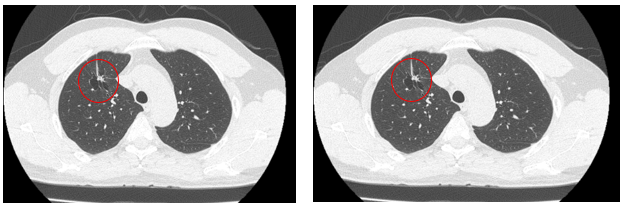

Hình 2: Hình ảnh chup cắt lớp vi tính ngực thấy khối u thùy trên phổi phải kích thước 12x18 mm, bờ tua gai, ít thay đổi so với phim chụp

Siêu âm hạch vùng cổ: Hạch thượng đòn trái tăng kích thước 20mm, mất cấu trúc rốn hạch, phá vỡ xâm lấn vỏ bao

Nhận xét sau 3 tháng điều trị TKIs: Sau 03 tháng điều trị, khối u ổn định về kích thước tuy nhiên hạch thượng đòn tăng kích thước, chất chỉ điểm u tăng cao so với trước điều trị.